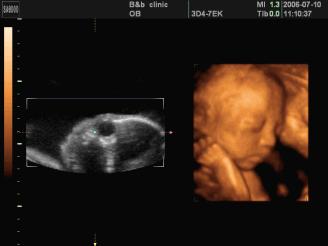

●四维彩超

四维彩超能够对胎儿进行动态、立体超声检查,显示胎儿的面部、各器官的发育情况,甚至胎儿在母体里的状态也可以观察到;对胎儿畸形,如唇裂、腭裂、骨骼发育异常等能早期诊断。另外还能制作成光盘,让宝宝拥有最完整的0岁相册,留下永久的记忆。